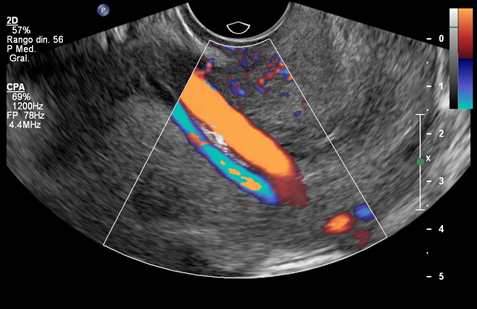

Here, we present the case of a nulliparous, 37-year-old patient diagnosed with type 3 vasa previa at 20+2 weeks’ gestation. This was a spontaneous pregnancy in a patient with no medical conditions who presented at the anomaly scan. The fetal anatomy was normal, and the location of the placenta was anterior, not previa nor low-lying. The cord insertion was marginal at the inferior edge of the placenta. A transvaginal ultrasound was performed for the measurement of the cervical length for preterm birth risk assessment and vasa previa screening, according with our institutional protocol. A large vessel crossing over the internal cervical os was identified. The placenta and cord insertion were re-examined, confirming a single placental lobe and a marginal cord insertion. The case was thus oriented as type 3 vasa previa and monthly follow-up ultrasounds were scheduled. Two vessels overlying the cervix were identified at 28 weeks’ gestation (Figure 1). Both vessels emerged from the placenta, close to the cord insertion, and followed a posterior-lateral right direction while crossing over the cervix. The larger vessel showed a venous flow, and the smallest vessel showed an arterial flow (Figure 2) (Figure 3). Further antepartum surveillance included weekly ultrasounds and non-stress tests (NST) from 32 to 36 weeks. The patient was asymptomatic, and the cervical length remained stable between 31and 33mm. Amniotic fluid index and fetal growth were normal, and NST showed a normal fetal cardiac frequency and pattern, as well as absence of uterine contractions.

Figure 3 Transvaginal ultrasound in a case of type 3 vasa previa. Color Doppler image showing a smaller vessel running over the internal cervical os and pulsed wave Doppler evaluation of this vessel, suggesting an arterial wave form.